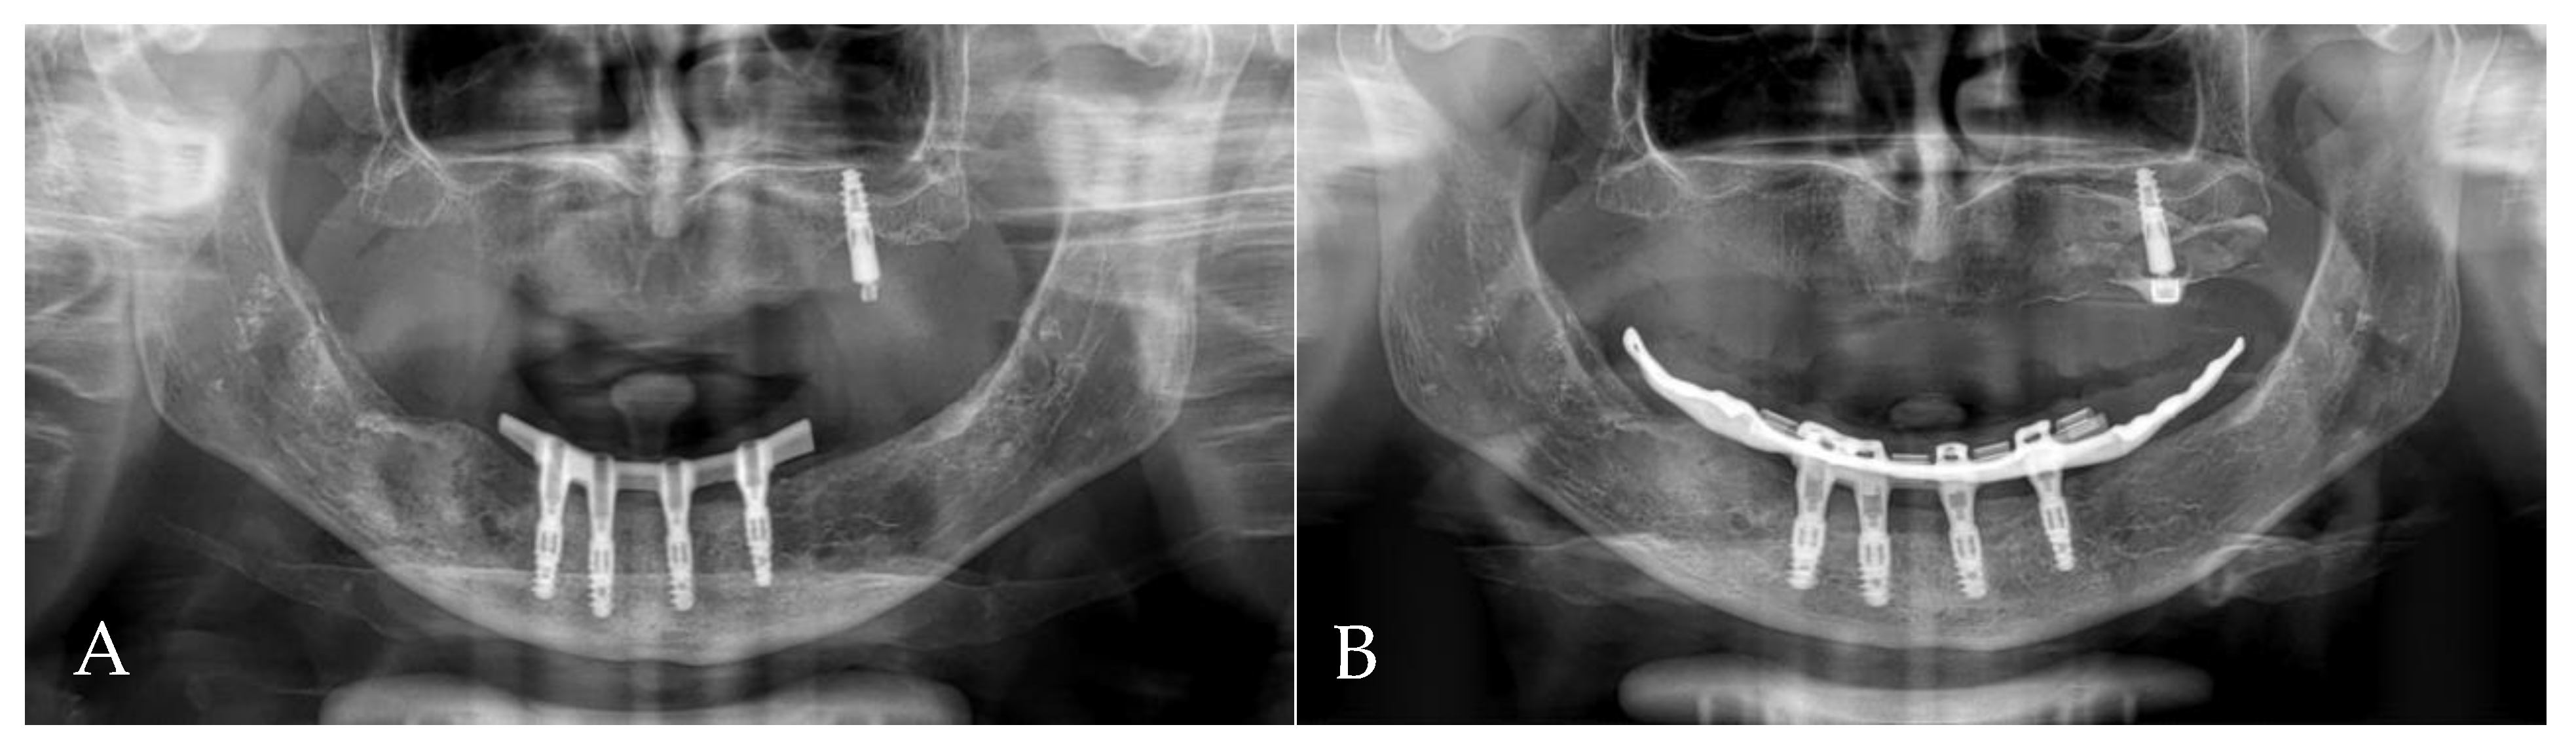

- The present case report described the treatment process of a patient with periodontitis, including immediate implantation in the infected region, soft tissue augmentation using free gingival grafts and the ultimate placement of a bar-retained overdenture as the final restoration. After two years of observation, despite questionable hygiene, no symptoms of gingival inflammation were detected. The orthopantomogram did not show any bone resorption.